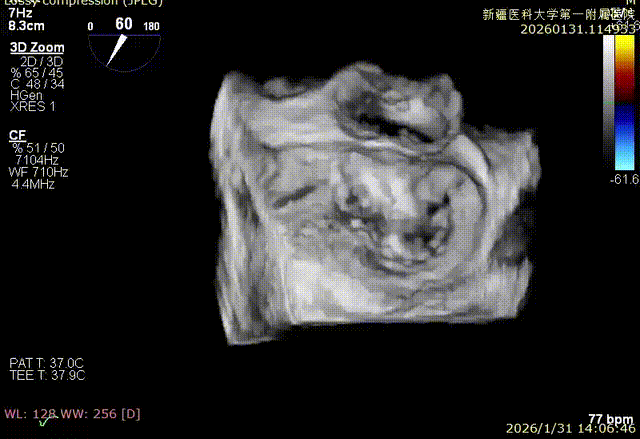

3D enface 切面

3D enface观察反流

3D enface 完成Orientation调整

3D enface反流充分降低

3D enface 观察后叶栓系